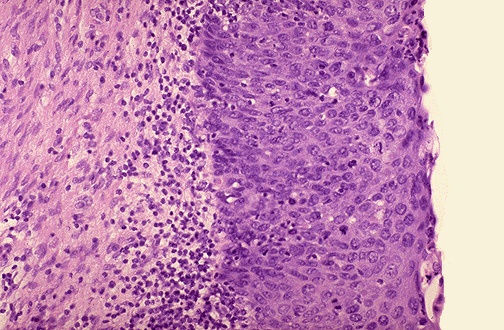

| When the entire epithelium is dysplastic and no normal epithelial cells are present, then the process has gone beyond dysplasia and is now neoplasia. If the basement membrane is still intact, as shown here, then the process is called "carcinoma in situ" because the carcinoma is still confined to the epithelium. Neoplastic epithelium is termed carcinoma. |